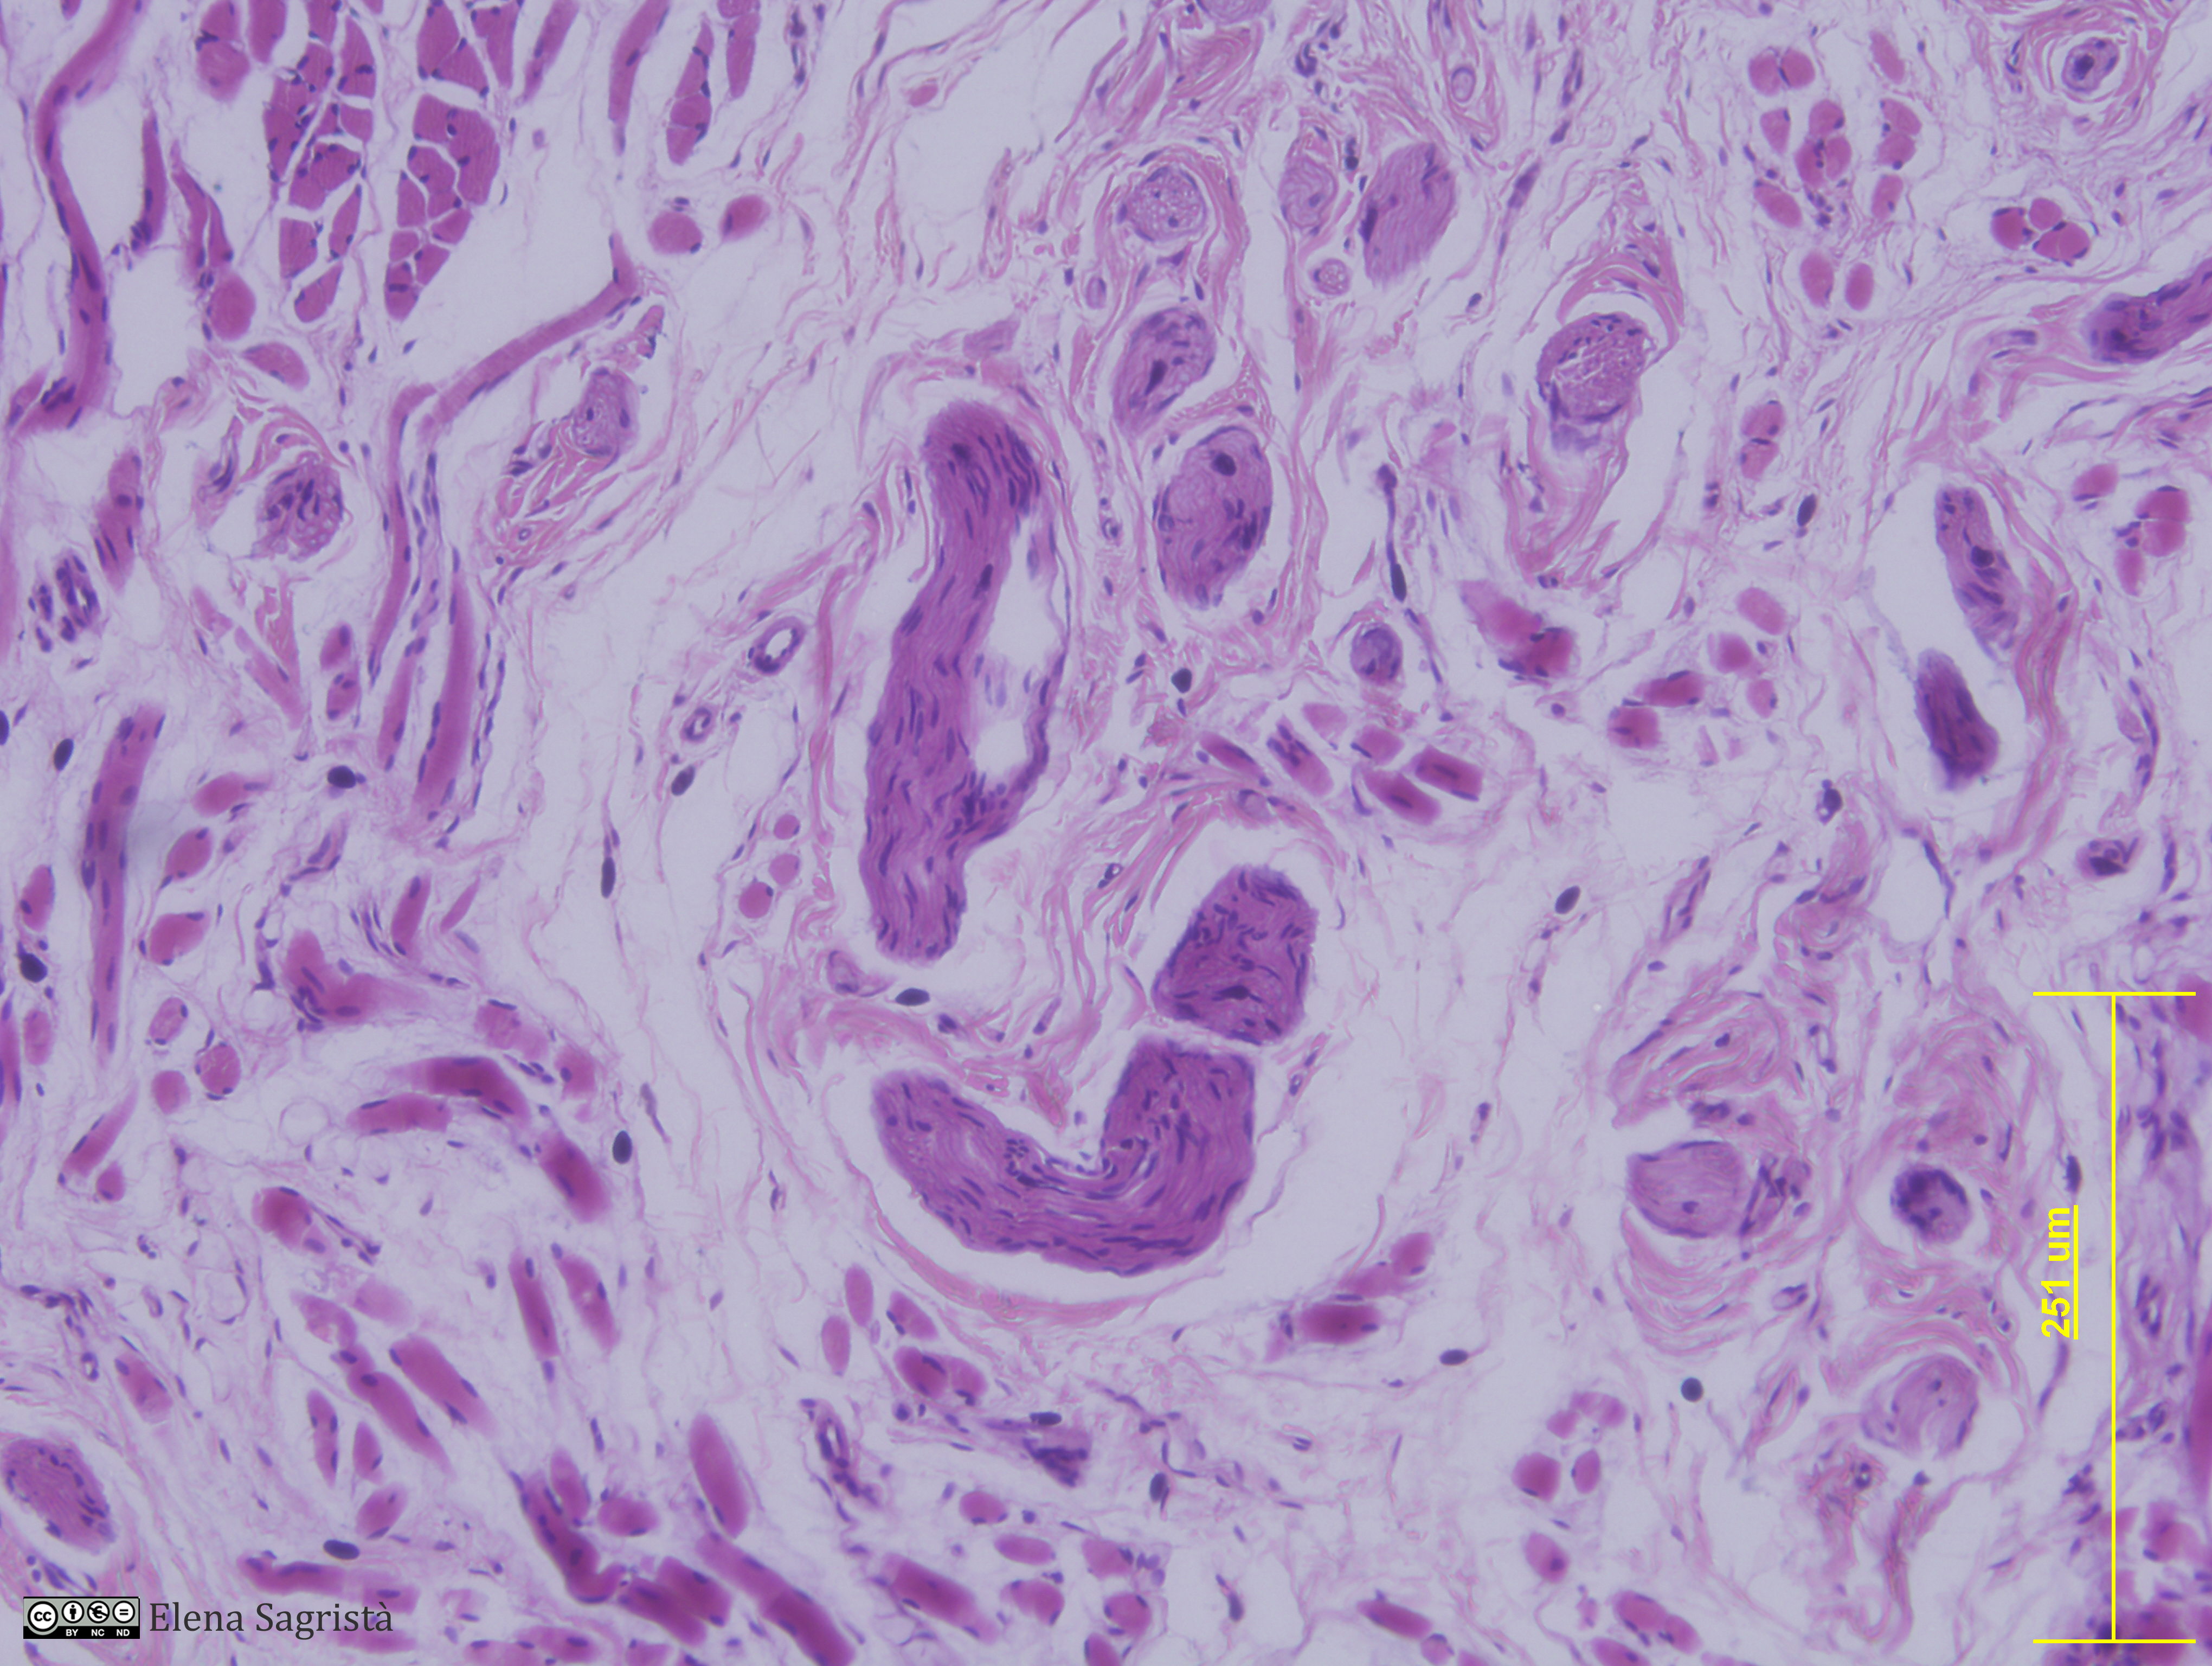

Histologia imatges: 09 Teixit nerviós perifèric

Imatges de preparacions histològiques de Teixit nerviós perifèric. Microscopia òptica.